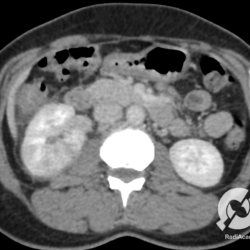

Não se trata da mesma paciente anterior, vejam que os cálculos coraliformes são diferentes. Mas a tomografia, principalmente na reconstrução coronal, mostra muito bem os cálculos renais. Lembrando: perceberam os cálculos menores no rim direito, que aliás é maior e tem uma densificação perinéfrica inferior? É bom ficarem espertos. Existe uma pielonefrite associada à direita.